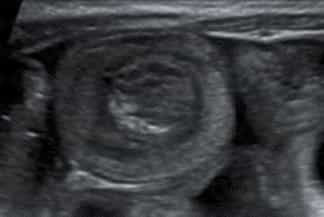

Texto alternativo para a imagem Figura 3. Créditos: Dra. Elazir Mota - Rio de Janeiro/RJ

Descrição das figura 2, 3 e 4: Ultrassonografia do abdome evidenciando o "sinal do alvo" - múltiplos anéis ecogênicos e concêntricos alternando-se com regiões hipoecoicas (os múltiplos anéis ecogênicos, na realidade, representam interfaces da parede intestinal), localizado na fossa ilíaca direita, caracterizando um quadro de invaginação intestinal ileocólica.

Exame de imagem: Por se tratar de patologia pediátrica, diante dessa suspeita diagnóstica, deve ser solicitada ultrassonografia (USG) de abdome que diagnostica quase a totalidade dos casos quando realizada por médico experiente (sua sensibilidade varia entre 95-100%, com especificidade de 88-100%). A invaginação aparece na USG como "massa" complexa e com anéis concêntricos hipo e hiperecoicos que se alternam (o sinal da rosquinha ou do alvo ). Nas imagens em eixo longo, a intussuscepção lembra um rim no qual o "córtex renal" representa a intussuscepção edematosa hipoecoica e o "seio renal" corresponde à gordura mesentérica invaginada (sinal do pseudorrim ).